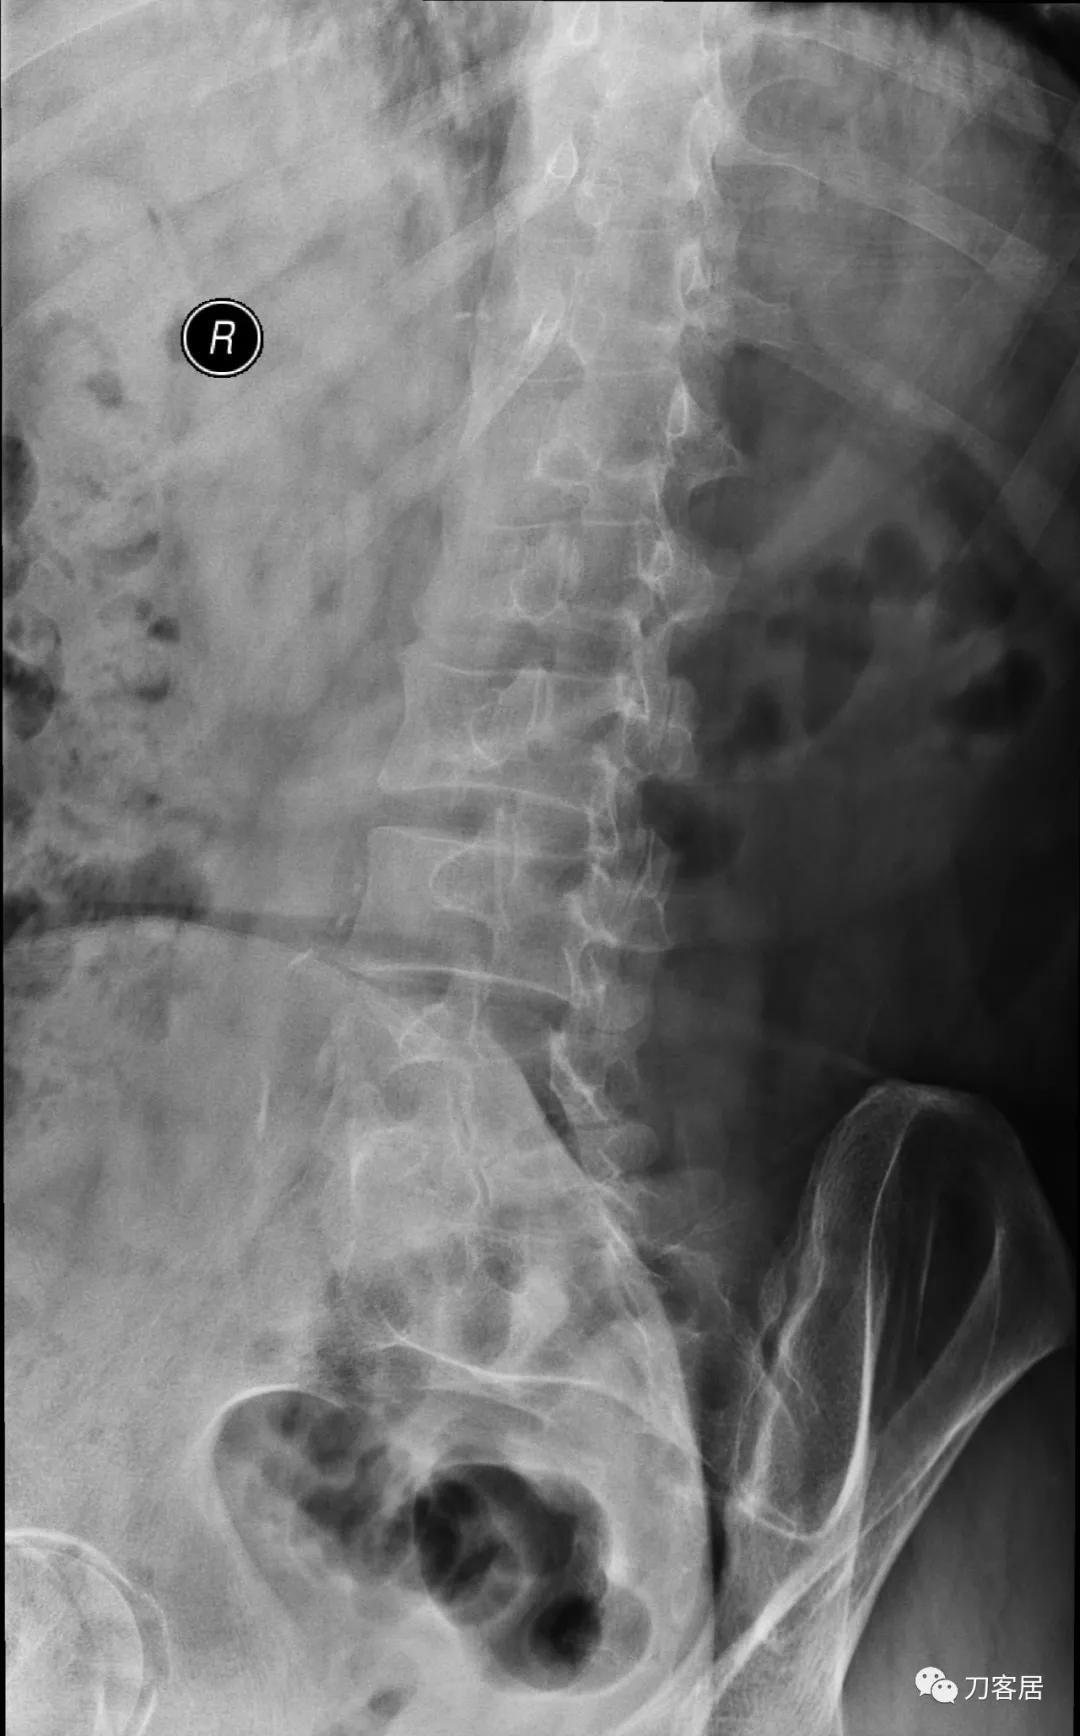

图7. 20210616术前腰椎右斜位X线片

图8. 20210616术前腰椎左斜位X线片